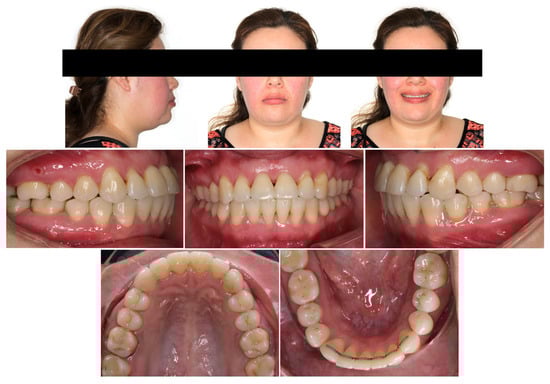

2.1. Diagnosis and Etiology